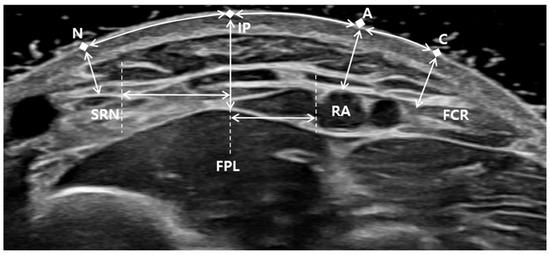

The preliminary needle IP and virtual needle pathway perpendicular to the surface were examined using ultrasonography. The safety of the needle insertion was verified by measuring the distance from the virtual needle pathway to the medial margin of the SRN and lateral margin of the RA. Additionally, the surface points of the SRN, RA, and FCR tendon perpendicular to the skin were marked (Figure 2). The distance between the IP and each surface point was then measured. The distance from the FPL muscle, SRN, and RA to each surface point was measured as the depth of each structure. In addition, the surface distance between the RA and lateral margin of the FCR tendon was measured in cases of difficulty with RA palpation.

Figure 2. Transverse view of ultrasonographic image of the forearm at the distal third of the forearm. N, skin surface point from SRN; IP, preliminary needle insertion point; A, skin surface point from RA; C, skin surface point from FCR; RA, radial artery; SRN, superficial radial nerve; R, radius; FPL, flexor pollicis longus; FCR, flexor carpi radialis.